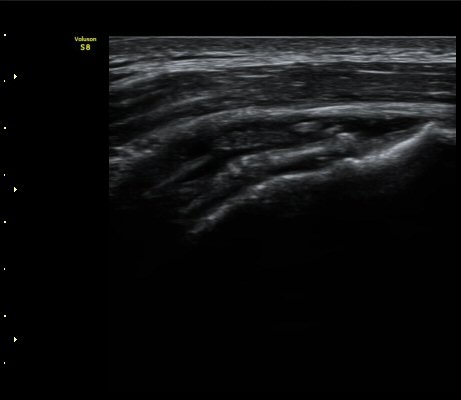

À̵ιڱ٠Ⱦ´Ü¸é°Ë»ç¿¡¼­ °üÀý³» ¼ö¾×Àú·ù´Â °üÂûµÇÁö ¾Ê´Â´Ù(»çÁø 1)